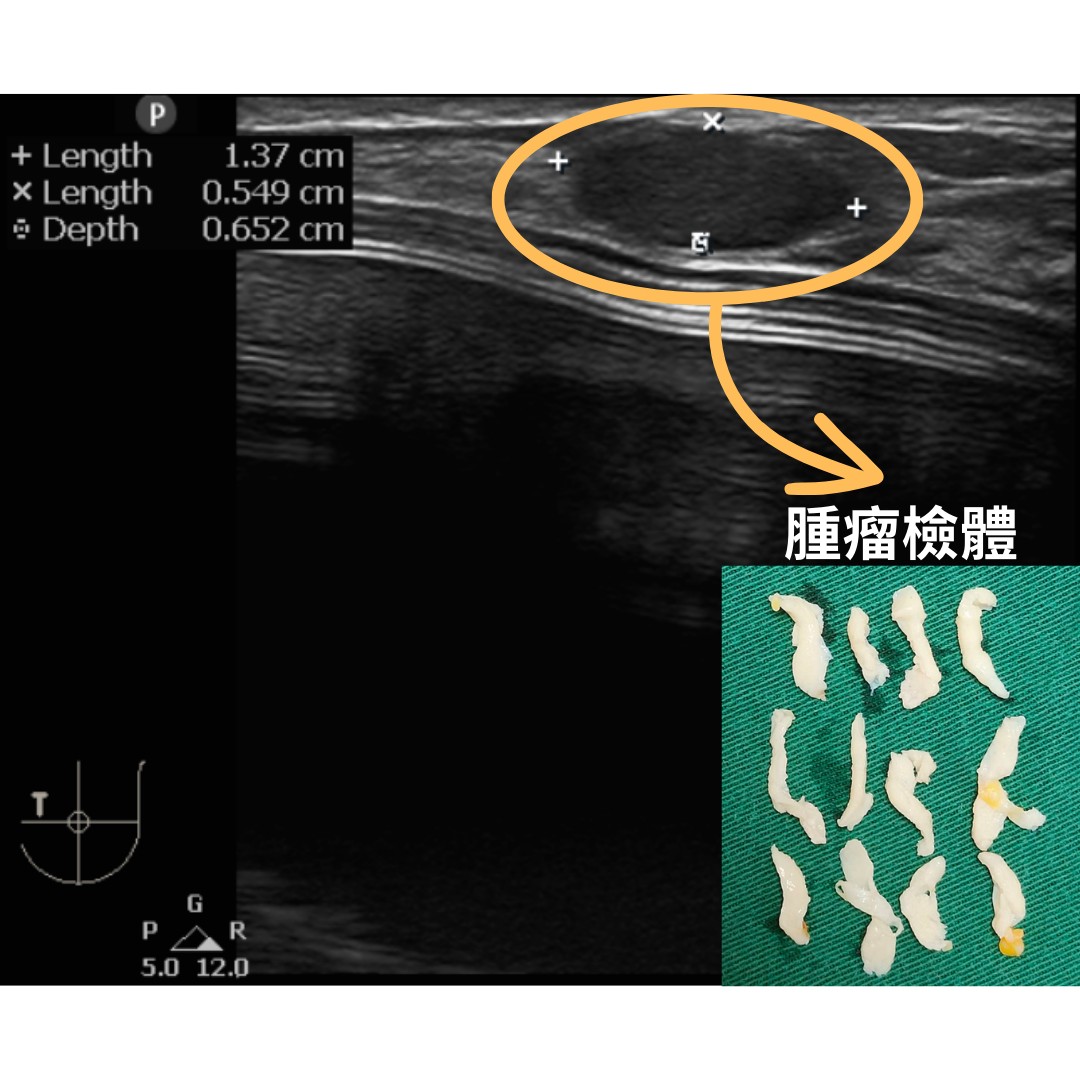

(注释:年約30歲的患者於複合式隆乳手術後半年,乳房即出現硬塊,經過醫病共同決策,採取微創清創手術,將脂肪硬塊取出。/圖片來源:杏妍診所)

杏妍診所曾收治一位約30歲的女性,她在3年前接受了複合式隆乳手術,但半年後發現硬塊卻束手無策。在尋找解決方案中,找到了黃院長。經共同討論後,決定採用內視鏡清創手術。黃院長指出,患者肌肉內有脂肪纖維化的硬塊,且受動作型疼痛影響,使得微創手術挑戰性高。手術需切除乾淨但不傷及肌肉,故需細緻技術。透過局部麻醉和超音波導引,手術僅10分鐘便準確完成。由於傷口小,患者迅速康復。